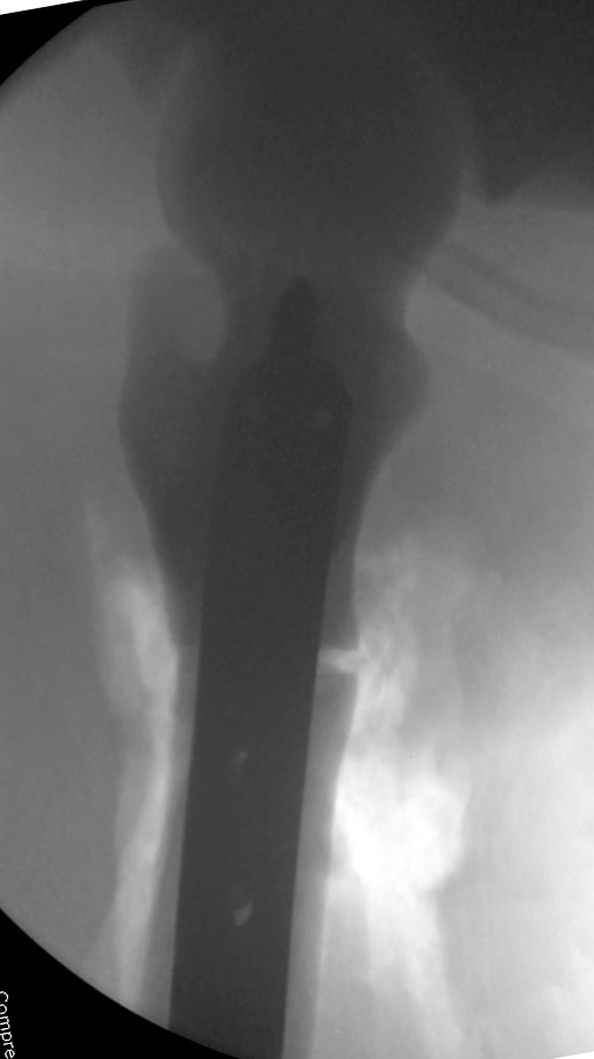

Наша тактика была бы - вертельный гамма стержень. Его длина 180 мм, должен поместиться до пластинки. Инструмент для формирования (не рассвреливания!) кнала, если он запаян, у нас есть.

Любой стандартный штифт для проксимального отдела бедра пройдет. TGN действительно из всех самый короткий, и поэтому предпочтительнее.

Не вызывает ли подозрение, что отсутствует медуллярный канал, как просверлить канал?

Канал, возможно, действительно запаян. Но разве большие проблемы его создать и рассверлить (если только это мраморная болезн?) Уверен, в вашей клинике есть для этого всё.

1. Верхушку б\вертела всктыть спицей и рассверлить каннюлированным инструментом (14 мм).

2. Если в диафизарной части канал запаян, то, используя сам штифт, введенный в проксимальный отломок, как центратор, по нему завести спицу в центр дистального отломка и сформировать канал, сначала тонкий 4 мм.

3. Гибкими (неканнюлированными) развертками диаметром 6,7 и 8 мм последовательно расширить канал.

4. Рассверливать каннюлироваными развертками по направляющей спице до нужного диаметра.